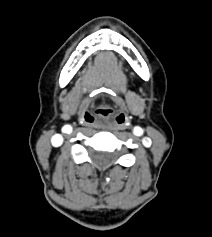

Мультиспиральная компьютерная томография – это высокоинформативный лучевой метод диагностики различной патологии мягких тканей шеи, включая воспалительные заболевания, травматические повреждения и опухолевые процессы. КТ позволяет оценить состояние щитовидной железы, паращитовидных желез, гортани, верхней части пищевода, магистральных сосудов шеи, шейных лимфоузлов и окружающих мягких тканей.

Метод КТ основан на применении рентгеновского излучения. Однако в отличие от обычного рентгена, при котором снимки производятся в одной плоскости, при КТ излучатель рентгеновских лучей постоянно двигается вокруг объекта исследования, проводя сканирование в различных плоскостях, а затем трансформируя полученные данные в цифровые трехмерные изображения. Это дает возможность визуализировать органы и ткани в мельчайших подробностях, а с помощью объемных 3D-реконструкций наглядно оценить пространственное расположение органов и патологических образований.

Рентгеновские лучи лучше всего поглощаются плотными структурами, такими как костная ткань. Поэтому кости хорошо видны на снимках КТ. Это делает компьютерную томографию незаменимой при необходимости обследования, в частности, костного скелета гортани. Однако для улучшения визуализации мягких тканей требуется введение специального контрастного препарата, поэтому КТ мягких тканей шеи проводится с контрастным усилением.

Для контрастирования используется йодсодержащее контрастное вещество, которое в составе рентгеноконтрастного препарата вводится в вену пациенту непосредственно во время исследования. Благодаря способности контраста поглощать рентгеновские лучи на снимках КТ хорошо контрастируются кровеносные сосуды и опухолевые образования, имеющие, как правило, развитую сосудистую сеть. Методика внутривенного болюсного контрастирования помогает обнаружить воспалительные изменения, отличить доброкачественные опухоли от злокачественных, выявить поражение лимфатических узлов и степень прорастания опухоли в магистральные сосуды и окружающие ткани.